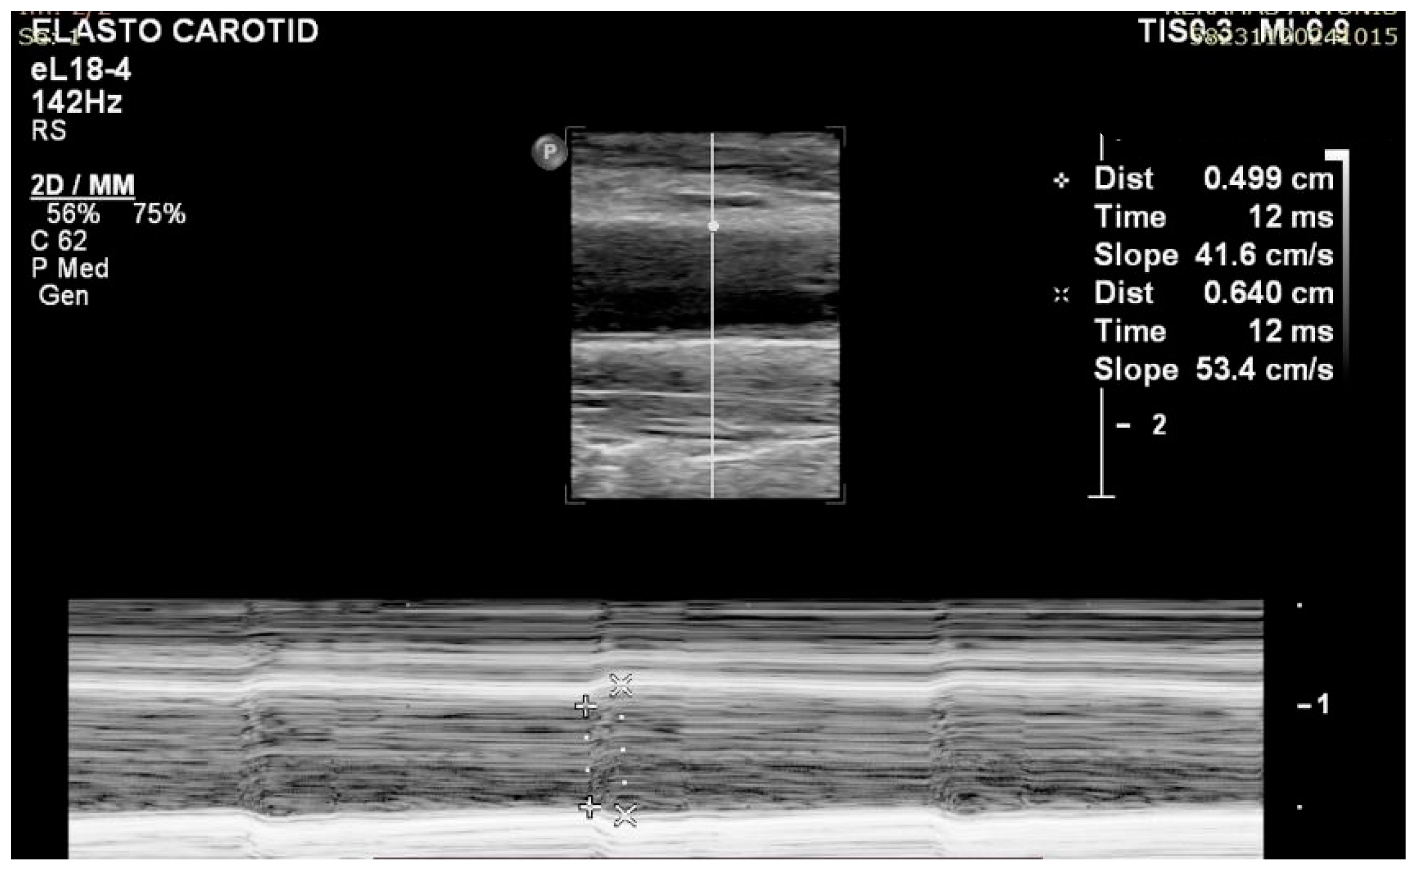

- Measurements during systolic and diastolic cardiac phases: A published case reports a difference of almost 60% between the two phases, with the systolic YM to be up to 130 kPa [65]. It seems that the shear wave speed in the carotid artery increases with blood pressure throughout the cardiac cycle, resulting in a higher stiffness during the systole compared to diastole.